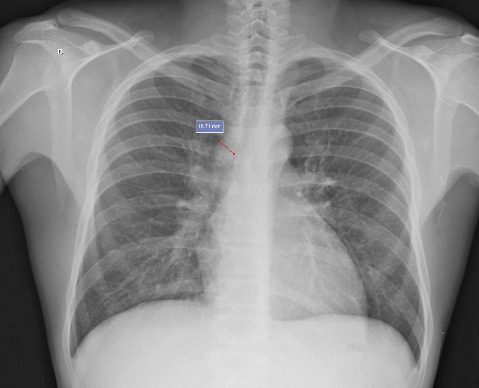

【傍気管線増大の画像】

【傍気管線増大の画像その2】(リンパ節腫大)

Right paratracheal stripe | Radiology Reference Article | Radiopaedia.org